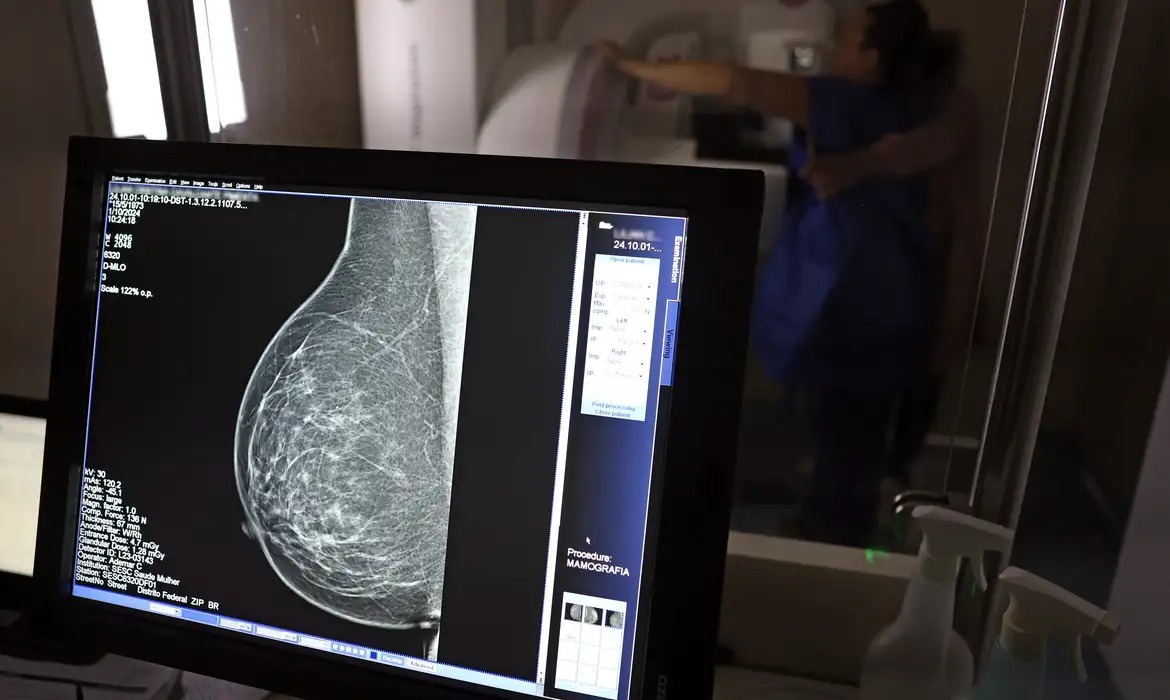

O Ministério da Saúde passou a recomendar o acesso a mamografia, via Sistema Único de Saúde (SUS), para mulheres de 40 a 49 anos – mesmo que não haja sinais ou sintomas de câncer de mama. De acordo com a pasta, a faixa etária concentra 23% dos casos da doença, e a detecção precoce aumenta as chances de cura.

Até então, a orientação era que o exame fosse feito a partir dos 50 anos.

As mamografias via SUS em pacientes com menos de 50 anos, de acordo com a pasta, representam 30% do total, o equivalente a mais de 1 milhão apenas no ano de 2024.

Outra medida anunciada é a ampliação da faixa etária para o rastreamento ativo – quando a mamografia é solicitada de forma preventiva a cada dois anos. A idade limite, até então, era 69 anos. Agora, passa a ser 74 anos. Dados do ministério revelam que quase 60% dos casos de câncer de mama estão concentrados entre 50 e 74 anos.

Os números mostram que, em 2024, cerca de 4 milhões de mamografias para rastreamento e 376,7 mil exames diagnósticos foram realizados no SUS.